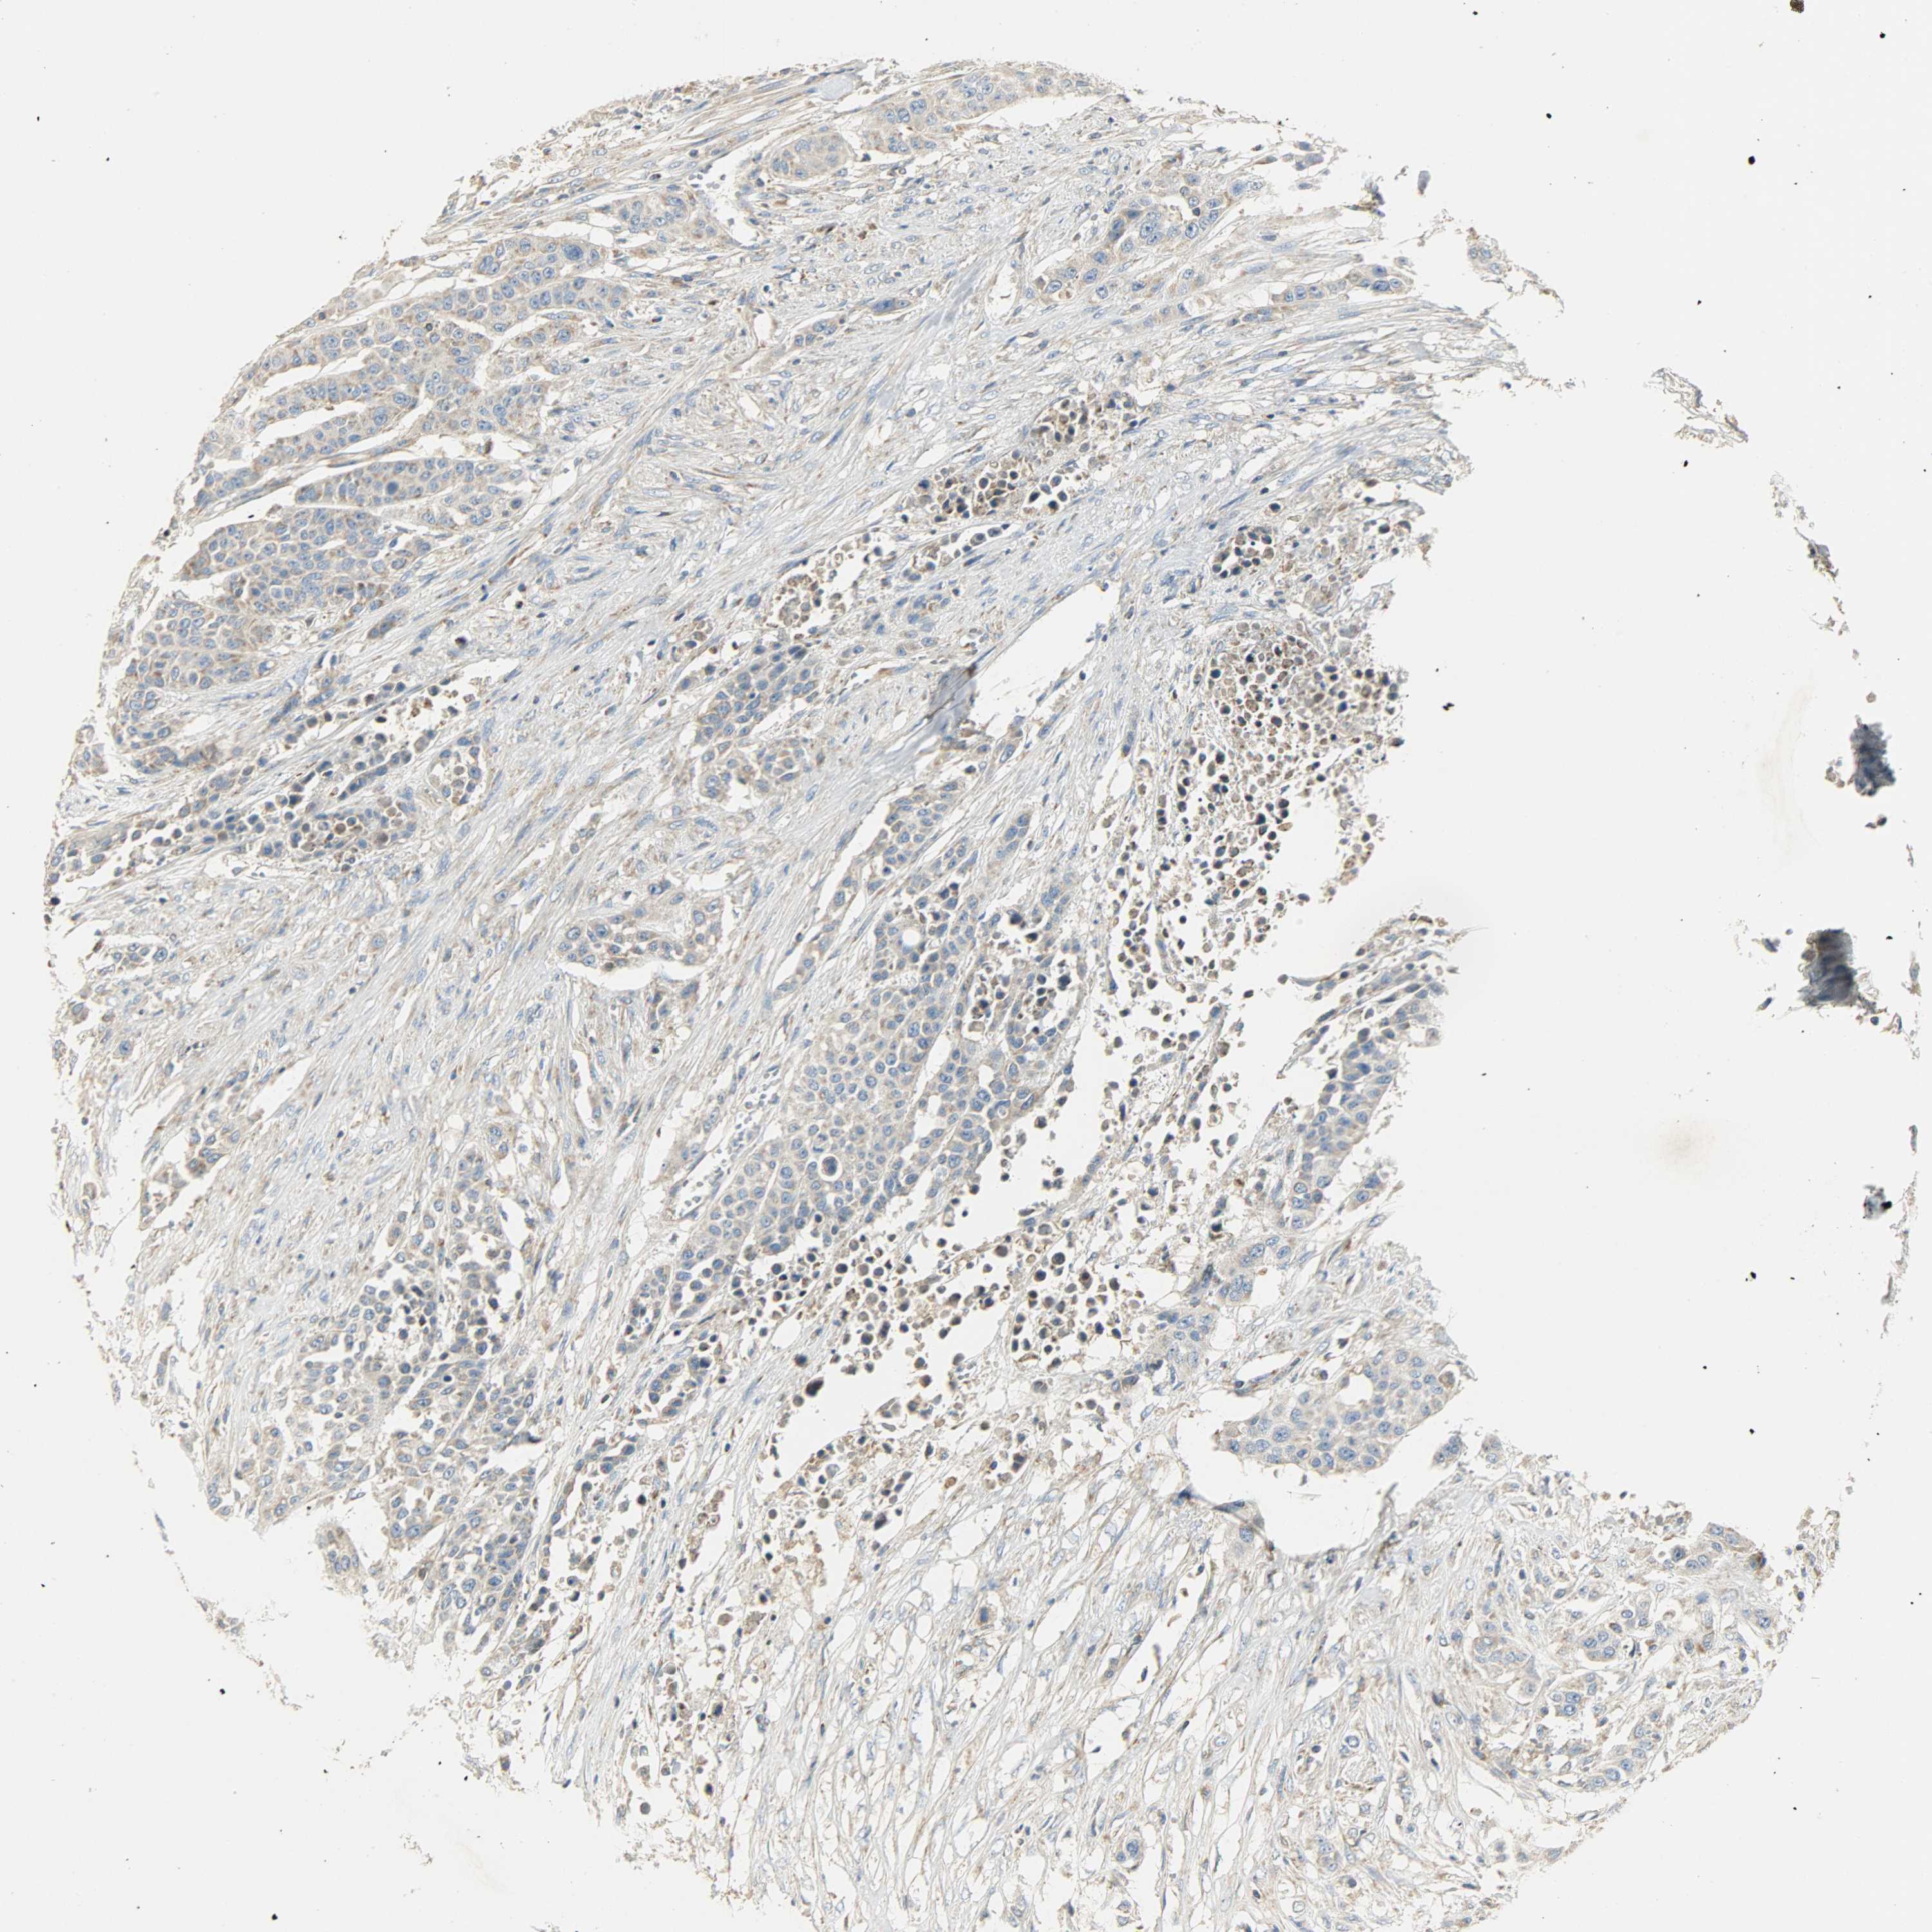

UROTHELIAL CANCER - Protein expressioni

A mouse-over function shows sample information and annotation data. Click on an image to view it in a full screen mode. Samples can be filtered based on level of antibody staining by selecting one or several of the following categories: high, medium, low and not detected. The assay and annotation is described here.

Antibody stainingi

Antibody staining in the annotated cell types in the current human tissue is reported as not detected, low, medium, or high, based on conventional immunohistochemistry profiling in selected tissues. This score is based on the combination of the staining intensity and fraction of stained cells.

Each image is clickable and will lead to virtual microscopy that enables deeper exploration of all samples and also displays staining intensity scores, fraction scores and subcellular localization as well as patient and tissue information for each sample.

Antibody HPA004829

Antibody CAB004975

Urothelial carcinoma, High grade

Urothelial carcinoma, Low grade